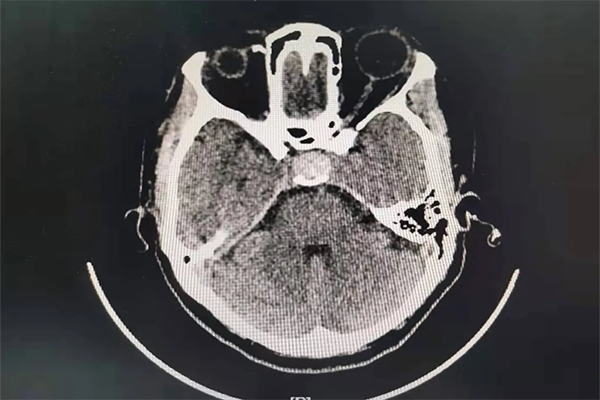

患者段女士,42歲。反復頭暈、眼花、心慌已經5月多了,5月前當地醫院頭顱CT未見明顯異常。1周前患者頭暈、眼花越發嚴重,輾轉多個醫院無果后,患者來到我院內科住院檢查,完善頭顱CT后,發現鞍區占位,考慮垂體腺瘤可能。

當外一科楊金雷主任到達內科時,已經找不到段女士的身影了。楊主任通過查看患者病歷,電腦閱讀CT,診斷患者為垂體腺瘤并出血可能,即患者可能存在瘤卒中。要求立刻打電話讓患者返回醫院接受正規系統的治療。

5個月的時間,CT結果提示鞍區占位病變,進行性增大,考慮瘤卒中可能。

完善檢查后,段女士被確診為無功能性垂體腺瘤并卒中。通過積極術前準備,楊金雷主任帶領的外一科醫護團隊,在省級專家指導及我院麻醉手術室的精誠協作下,為段女士開展了顯微鏡下經鼻蝶垂體腺瘤切除術。手術歷時1.5小時后順利結束。